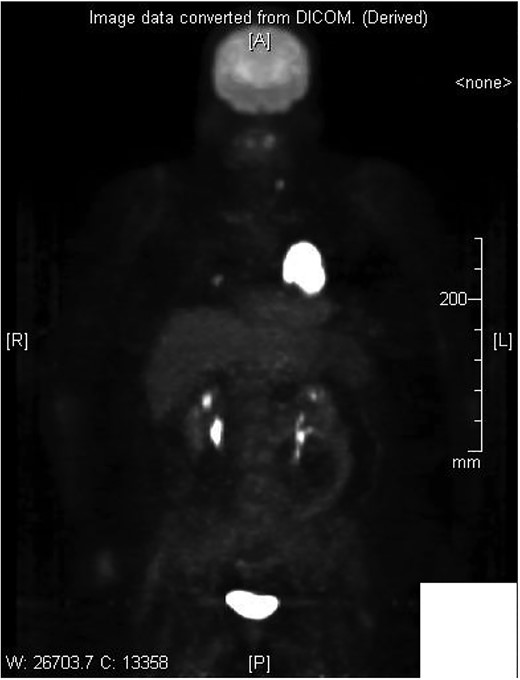

Cardiothoracic surgery team was consulted, and the patient underwent a pericardial window with 750 cc of serosanguinous fluid drained from her pericardial space. A chest tube placed status-post pericardial window, which initially continued to drain 500 cc of serosanguinous fluid, with fluid volume decreasing in the following 5 days with stable vital signs. The patient tolerated the switch to p.o. amiodarone and discharged upon her request to restart chemotherapy, after removal of her chest tube. Histopathology results of the pericardial fluid were positive for reactive mesothelial cells and chronic inflammation. Follow-up positron emission tomography (PET)/CT scan depicted increased uptake in the cardiac chamber (Fig. 4). Repeated echocardiography 2 months later depicted a return in pericardial fluid with the patient remaining hemodynamically stable with preserved ejection fraction.